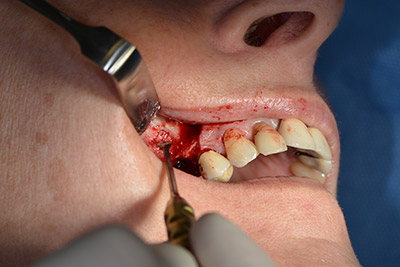

Хирургична процедура за имплантиране

Класическият разрез (крестално, букално освобождаване) и подготовката на мукопериостално ламбо осигуряват добра видимост.

Импланти Sky (Bredent) са използвани в този случай. Хирургичният протокол за тях изисква пилотно пробиване с дрил при 1200 rpm (Фиг. 9).